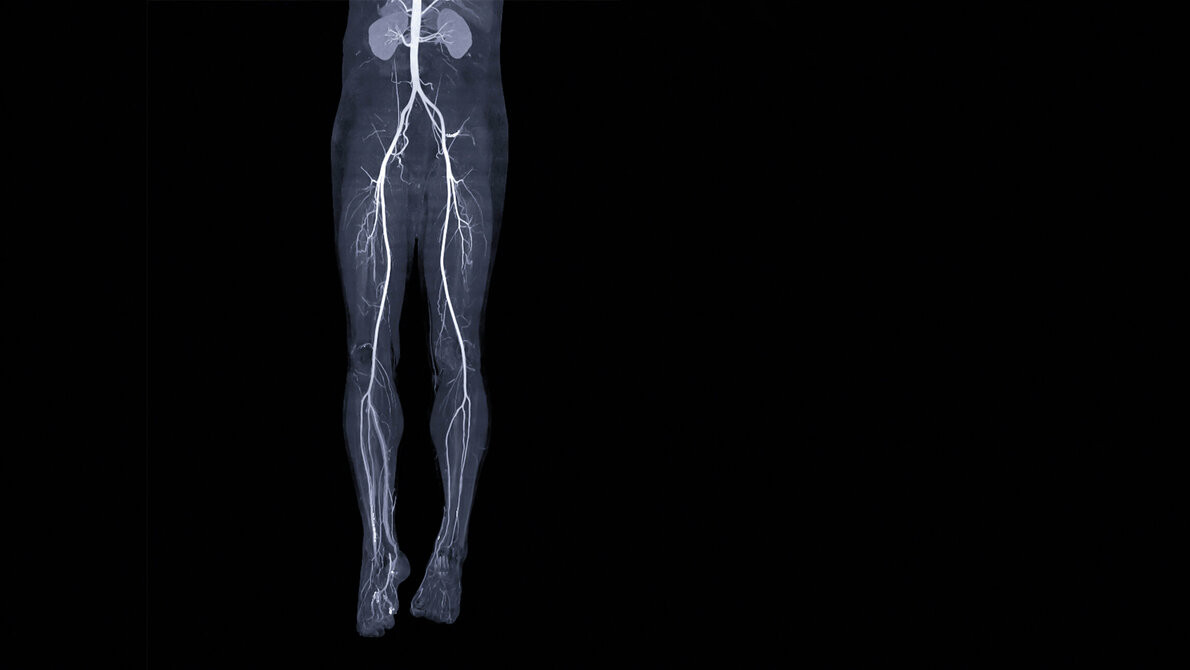

Patientenlagerung:

• Rückenlage

• Feet First (mit den Füßen in Richtung Gantry lagern)

• Beine wenn möglich parallel lagern

• Füße parallel lagern und zur besseren Stabilisierung sanft zusammenbinden

• Elevierte Arme (über dem Kopf lagern)

• Tischhöhe: Seitenlaser seitliche Oberschenkelmitte/Kniemitte